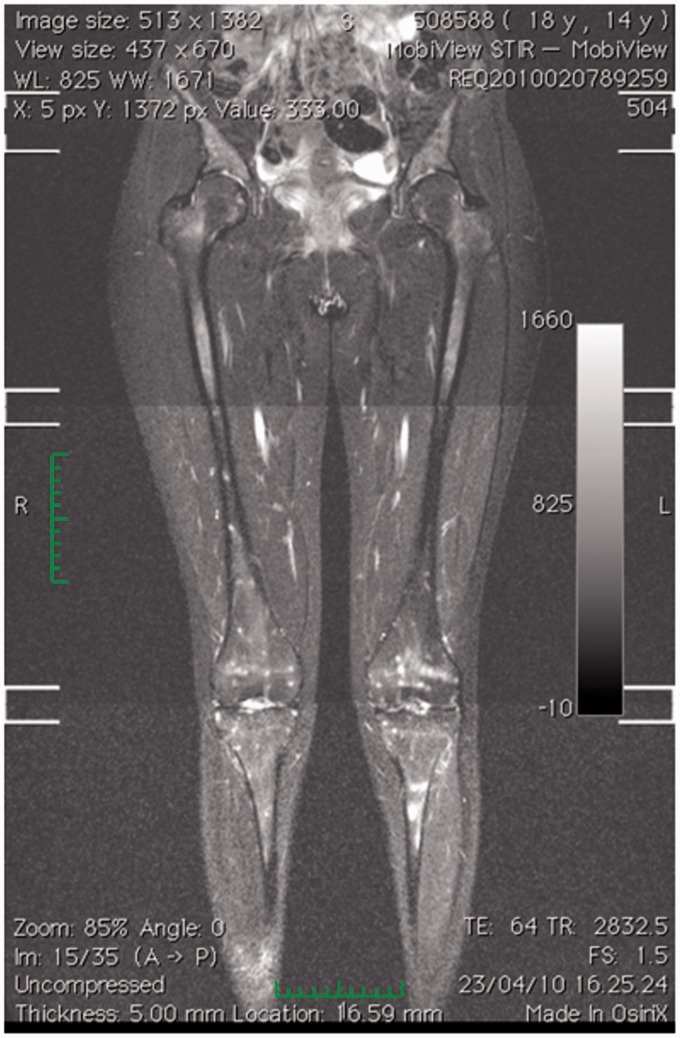

嗜吞噬细胞无原体是一种专性细胞内细菌,是人类粒细胞无原体病(HGA)的病原体,HGA是一种蜱传感染,通常表现为发热、不适、细胞减少、脾肿大和肝炎。在此,我们报告一例14岁的HGA女孩,其全身磁共振成像(MRI)显示了一个不寻常的图像,其特征是小的,广泛的标点毫米结节,t1加权低信号和STIR序列高信号。这一首次报道的发现可能代表了鉴定非典型传染病的另一种工具。

Anaplasma phagocytophilum, an obligate intracellular bacterium, is the causative agent of human granulocytic anaplasmosis (HGA), a tickborne infection usually manifesting as fever, malaise, cytopenia, spleen enlargement, and hepatitis. Herein, we report a case of a 14-year-old girl with HGA whose whole-body magnetic resonance imaging (MRI) disclosed an unusual picture characterized by small, widespread punctuate millimetric nodules, hypointense on T1-weighted and hyperintense on STIR sequences. This firstly reported finding may represent an alternative tool for identifying atypical infectious diseases.